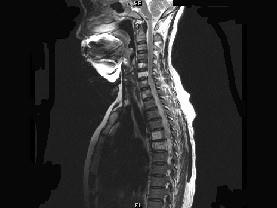

请结合提供图像,选择最佳选项 ( )A、退行性变B、脂肪瘤C、多发性骨转移D、骨血管瘤病E、骨结核

问题 请结合提供图像,选择最佳选项 ( )

选项 A、退行性变 B、脂肪瘤 C、多发性骨转移 D、骨血管瘤病 E、骨结核

答案 D